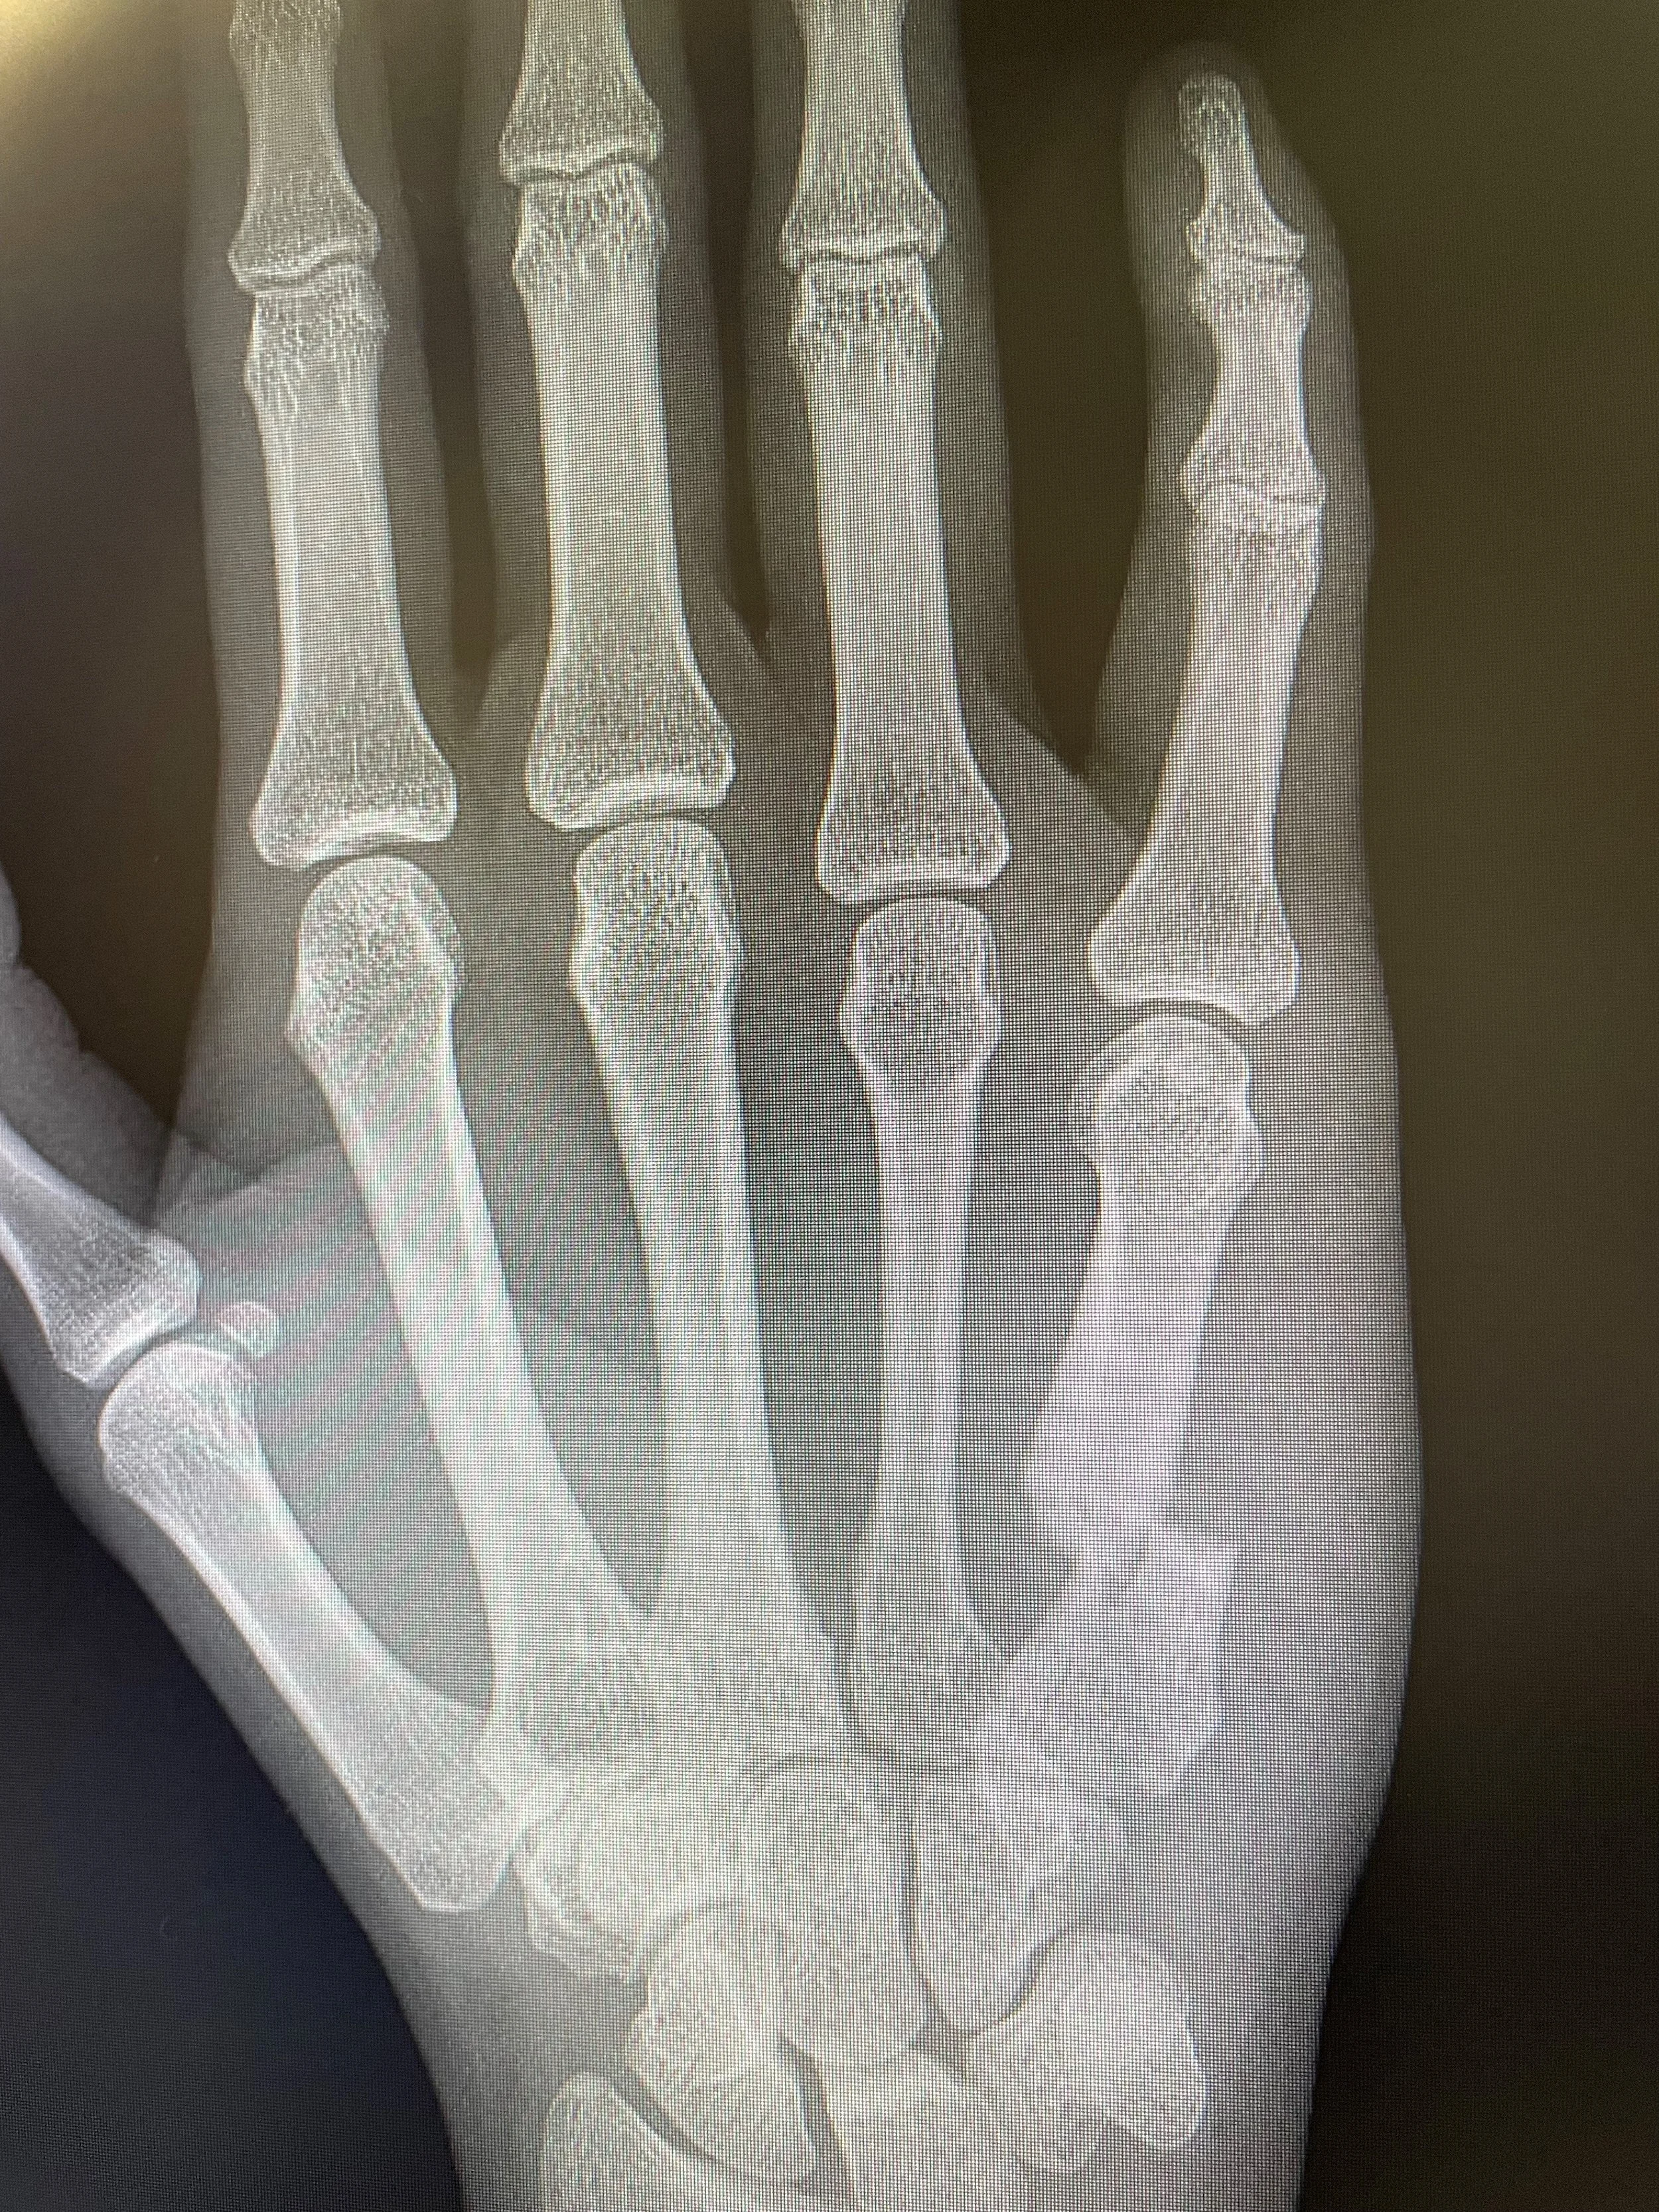

An X-ray image of a human hand showing the bones of the fingers, palm, and wrist.